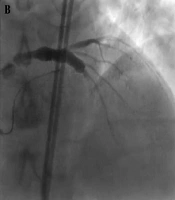

Evaluation of the Effect of ASD Closure Using the Device Method in Improving Echocardiographic and Clinical Parameters in Patients Over 40 Years of Age from 2016 to 2019

Sedigheh Saedi,

Nasim Nemati*

27

Oct

2025